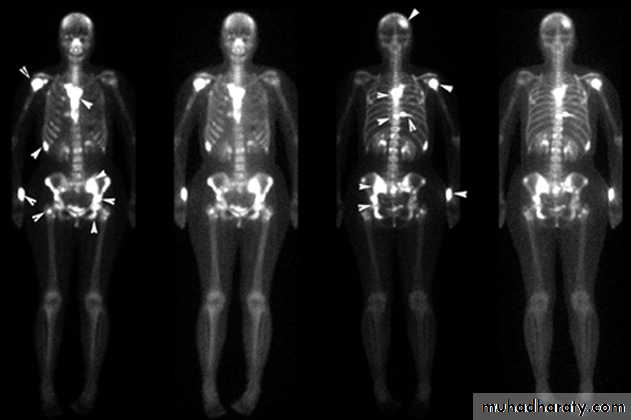

(3) Blood streams: it is by this route skeletal metastases occur. In order of the frequency the lumbar vertebrae, femur, thoracic vertebrae, rib and skull are affected and these deposits are generally osteolytic. Metastases may also commonly occur in the liver, lung, brain, and occasionally adrenal glands and ovaries.

This is described as cancer en-cuirasses when disease progress around chest wall. About 5% carcinoma in UK presented as locally advanced or symptoms of metastatic disease this figure is much higher in developing countries. These patients under goes staging evaluation so this will include a careful clinical examination, chest x-ray, CT scan chest and abdomen and isotope scan, bone scan.

This will be important for both prognosis and treatment. A patient with wide spread visceral metastases may obtain an increased length and quality of survival from systemic hormone therapy or chemotherapy but is unlikely to benefit from surgery as she will die from her metastases before local disease becomes a problem. In contrast, patients with relatively small tumors less than 5 mm in diameter confined to the breast and ipsilateral lymph nodes, rarely need staging beyond a good clinical examination as puck up rate for distant metastases is so low. Currently, a chest x-ray, full blood count , liver function test are all that recommended for screening of the patient with early breast cancer.